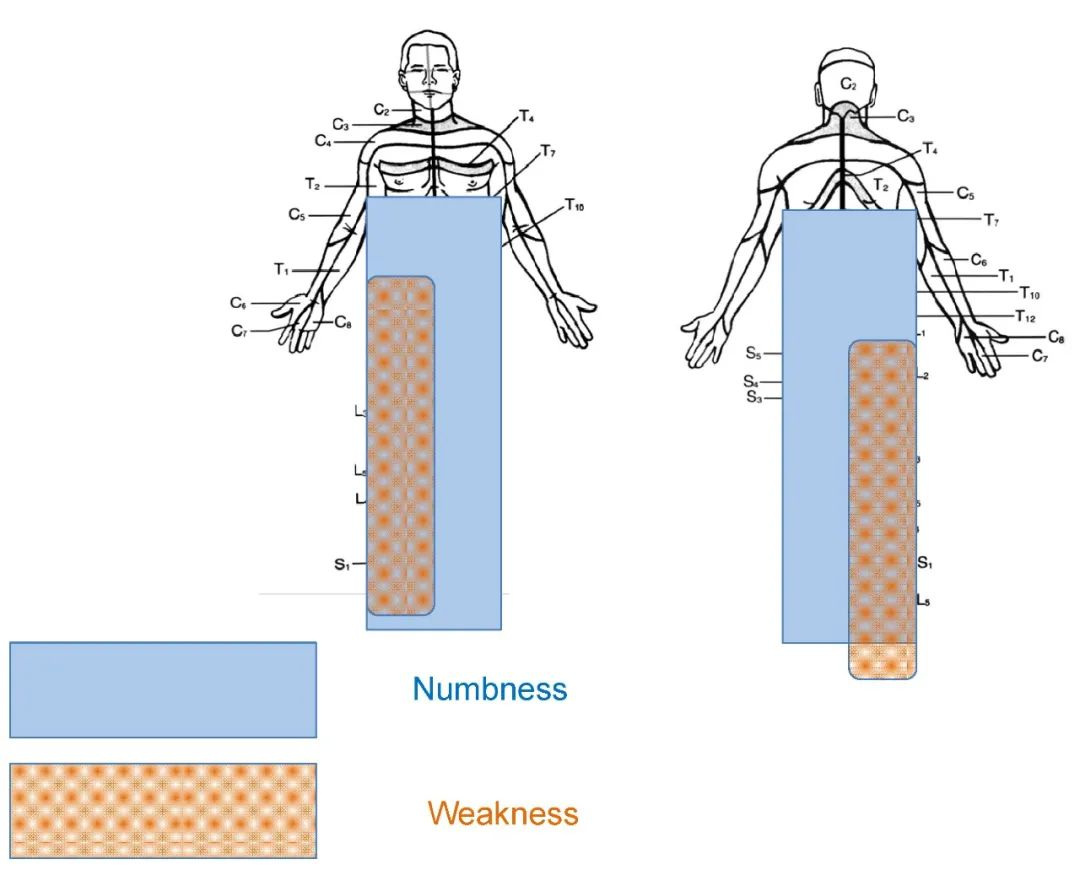

病史:M, 34 y/o

Numbness of right lower limb for 2 months, weakness for 1 week

Urination disorder

Thoracic spinal stenosis(T2-T3)